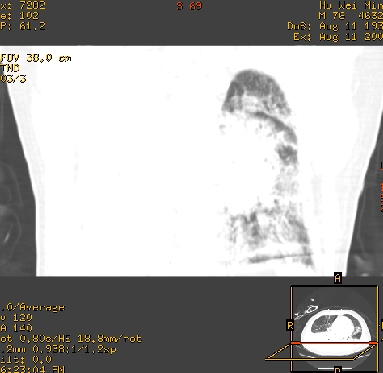

9号平片